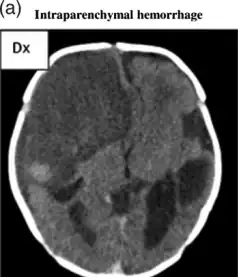

CT scan shows a very large intraparenchymal haemorrhage with mass effect and occupying most of the right frontal lobe -

Intraparenchymal hemorrhage -

CT-scan of intraparenchymal hemorrhage

Computed tomography (CT scan): A CT scan may be normal if it is done soon after the onset of symptoms. A CT scan is the best test to look for bleeding in or around your brain. In some hospitals, a perfusion CT scan may be done to see where the blood is flowing and not flowing in your brain.